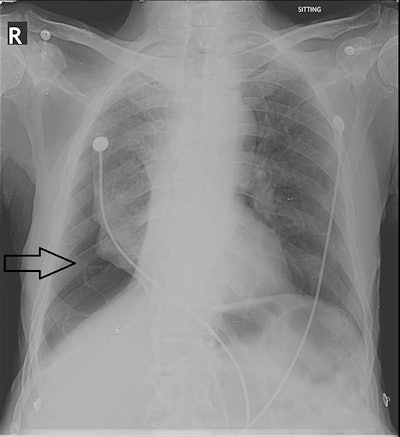

Pneumothorax is the presence of air or gas in the cavity between the lungs and the chest wall, which can cause the collapse of the lung. Chest x-ray is usually readily available and has high accuracy in detecting the condition. Rather than transporting patients from emergency settings to radiology departments, however, portable chest x-ray is commonly used to diagnose pneumothorax.

The group included 174 portable chest x-rays of patients acquired in the emergency room and intensive care units at their hospital that had been labeled positive for pneumothorax by a radiology resident and attending radiologist. Of the 174 patients, 139 (79.9%) were male and 35 (20.1%) were female. The mean age of patients was 45.6 years old.

According to the results, pneumothorax was reported by residents in 164 (94.25%) cases, while the attending radiologist reported it in 167 (96%) cases. The remaining 4% of cases were ultimately diagnosed on a chest CT scan. Concordance between the on-call residents and attending radiologists was 92.5% (p = 0.008), the researchers reported.